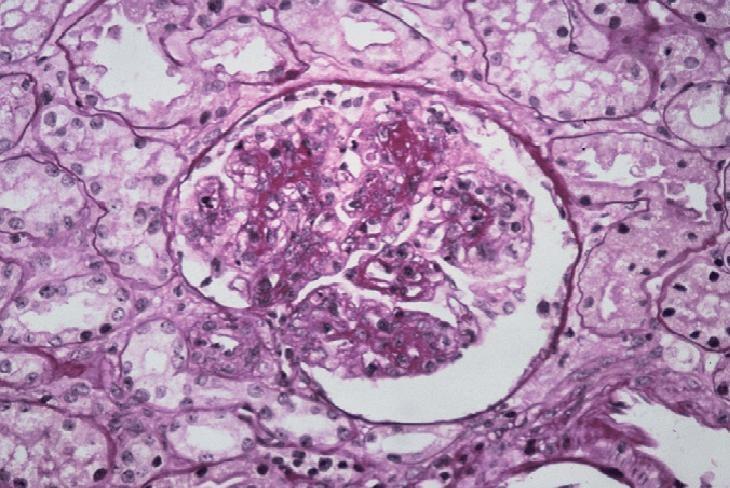

Glomerulonefritis mesangial

Membranoproliferativo

La glomerulonefritis mesangial y Membranoproliferativa son los tipos más frecuentes de enfermedades glomerulares, lo que conlleva también a la Amiloidosis secundaria. El deposito de inmunocomplejos en el tejido renal y la activación de las moléculas de adhesión de células T son los responsables de su patogenia.